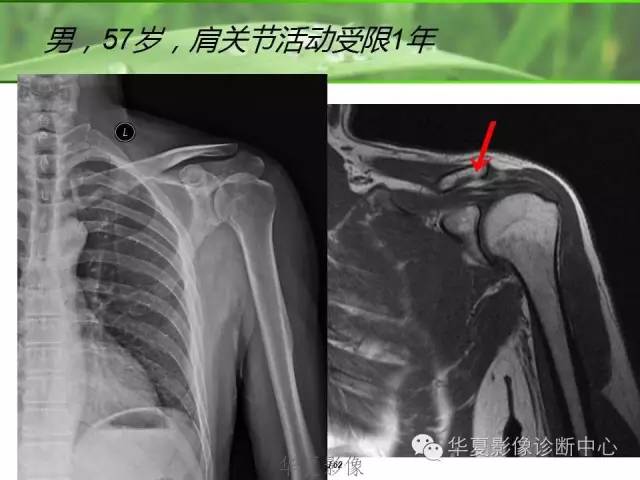

2.肩关节MRI检查

肩关节MRI检查可以确定肩关节周围结构信号是否正常,是否存在炎症,可以作为确定病变部位和鉴别诊断的有效方法。